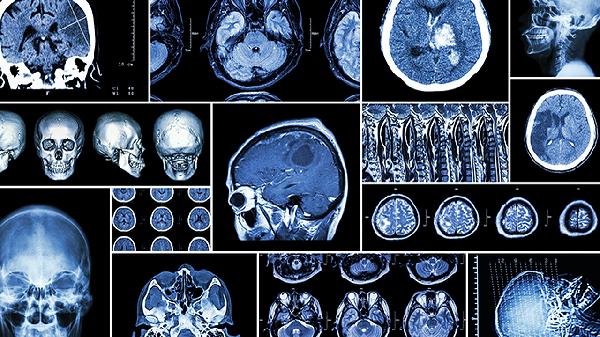

颈动脉或椎基底动脉系统微血栓可能导致突发的片段性遗忘,通常持续数分钟至数小时。可能伴随言语含糊或单侧肢体无力。需立即进行头颅CT或血管造影检查,阿司匹林和氯吡格雷是常用预防药物。

日常应保持均衡饮食,适量补充富含欧米伽3脂肪酸的深海鱼和抗氧化作用的蓝莓等食物。每周进行三次有氧运动促进脑部血液循环,避免长时间低头使用电子设备。若失忆发作频繁或伴随其他神经系统症状,需及时进行脑电图和核磁共振检查。建立规律的记忆训练习惯,如学习新语言或乐器演奏,有助于增强大脑认知储备。